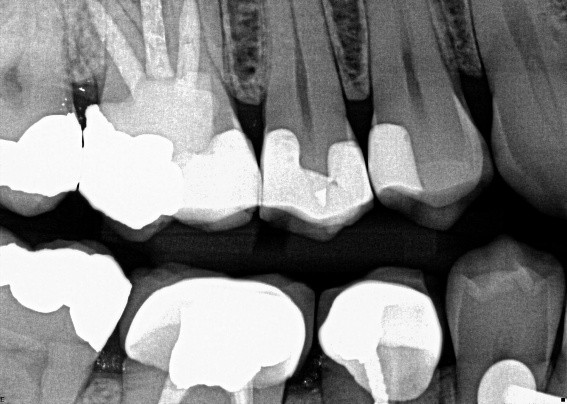

The radiograph shows evidence of